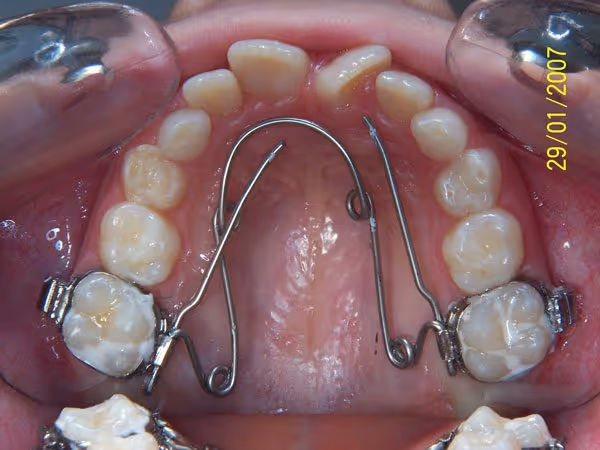

- Tous les 3 RDV, un contrôle général est à réaliser sur le QH. Le RRR (Retirer – Réactiver – Reposer) permet au praticien de rajouter au QH les informations perdues pendant son action et ceci jusqu'à l’obtention du résultat recherché.

- A chaque RRR un traitement thermique est à faire sur toute la longueur du QH à l'exception des bras. Ce traitement thermique redonne au fil ses qualités métallurgiques pour une nouvelle action.

- Afin de stabiliser le résultat acquis il faut le laisser le QH, au minimum, en passif autant qu’en actif (si 5 mois sont nécessaires pour finir le travail, il faut le laisser 5 mois supplémentaire sans activations).

4- Résultat final de l’action du Quad Hélix: